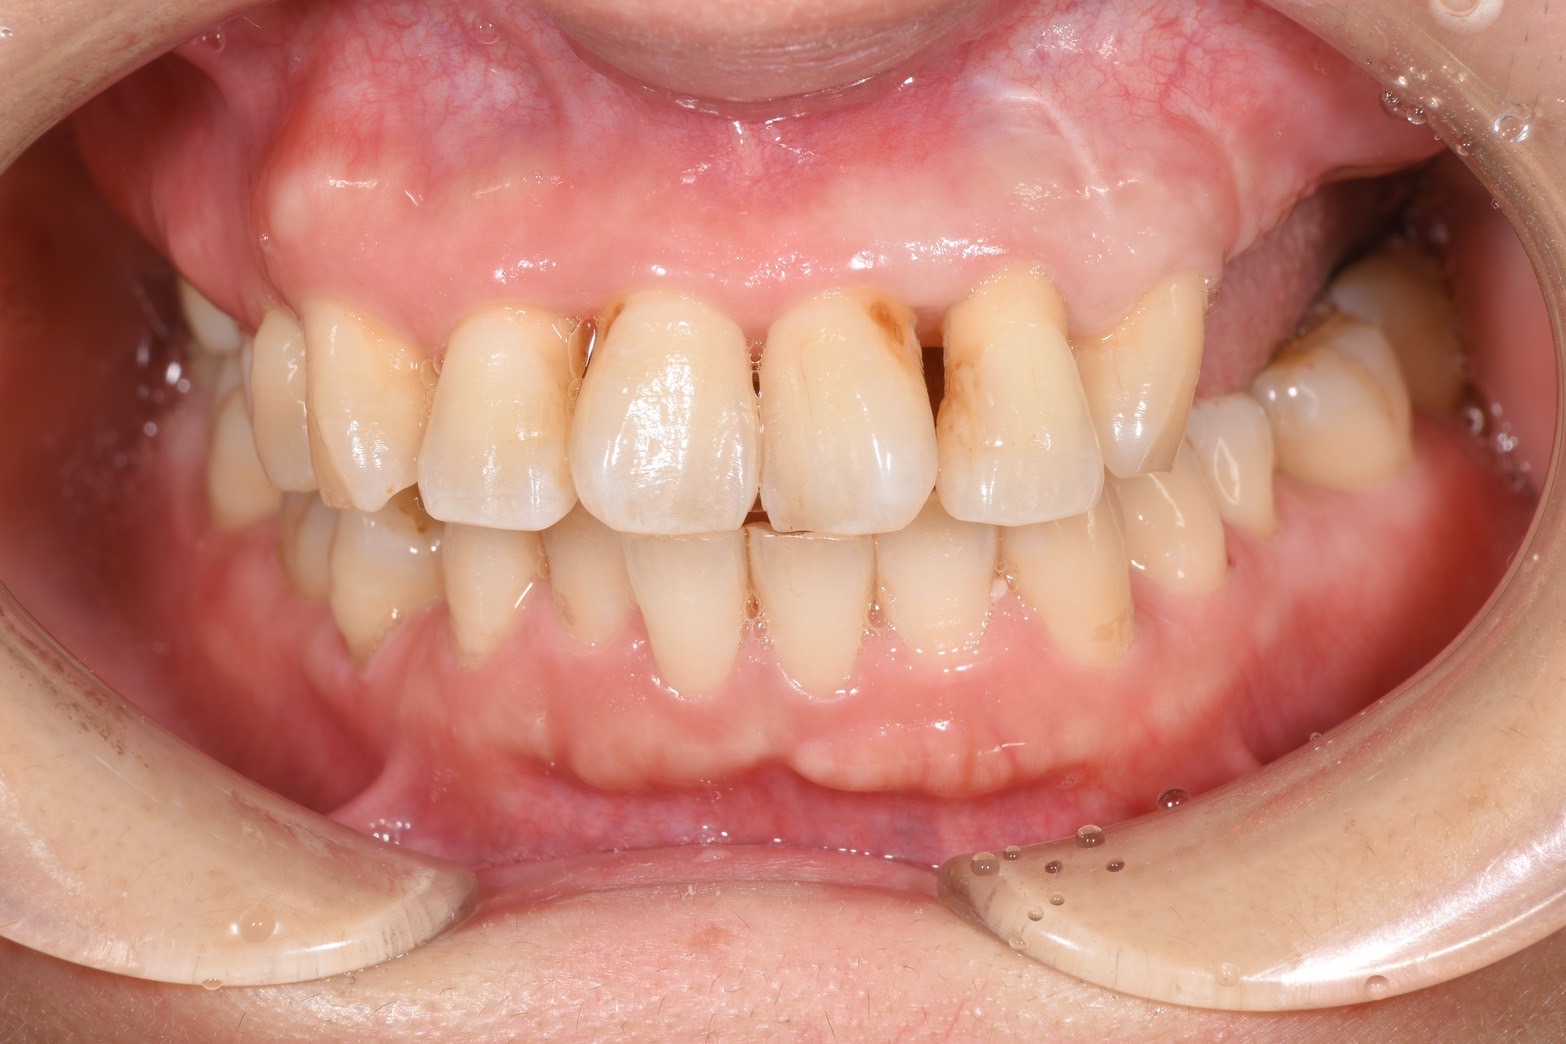

After

歯周病によって骨が無くなり、インプラントができない状態であったため、骨造成してインプラント治療を行いました。